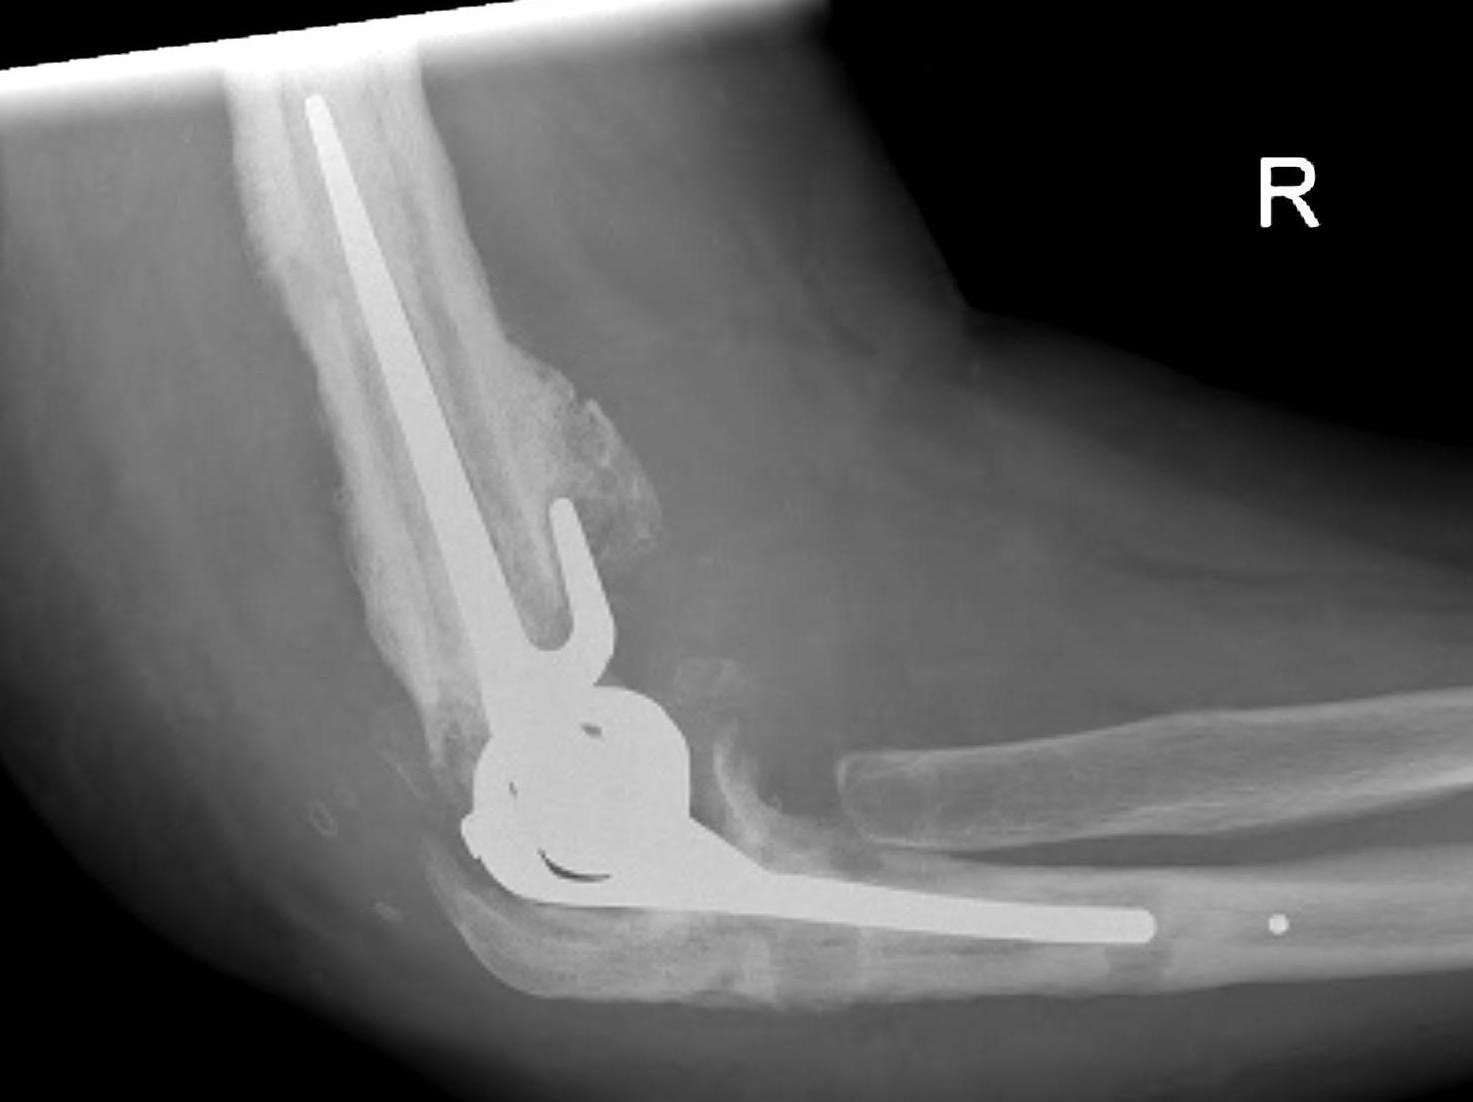

- systematic review of TEA with 10 years follow up

- 1429 elbows

- overall revision rate at 10 years 15%

- loosening at 10 years 13%

- infection 3%

- dislocation 4%

- nerve injury 2%

Aseptic Loosening

- systematic review of 3000 TEA

- loosening rates 10% for unlinked and 14% for linked prosthesis